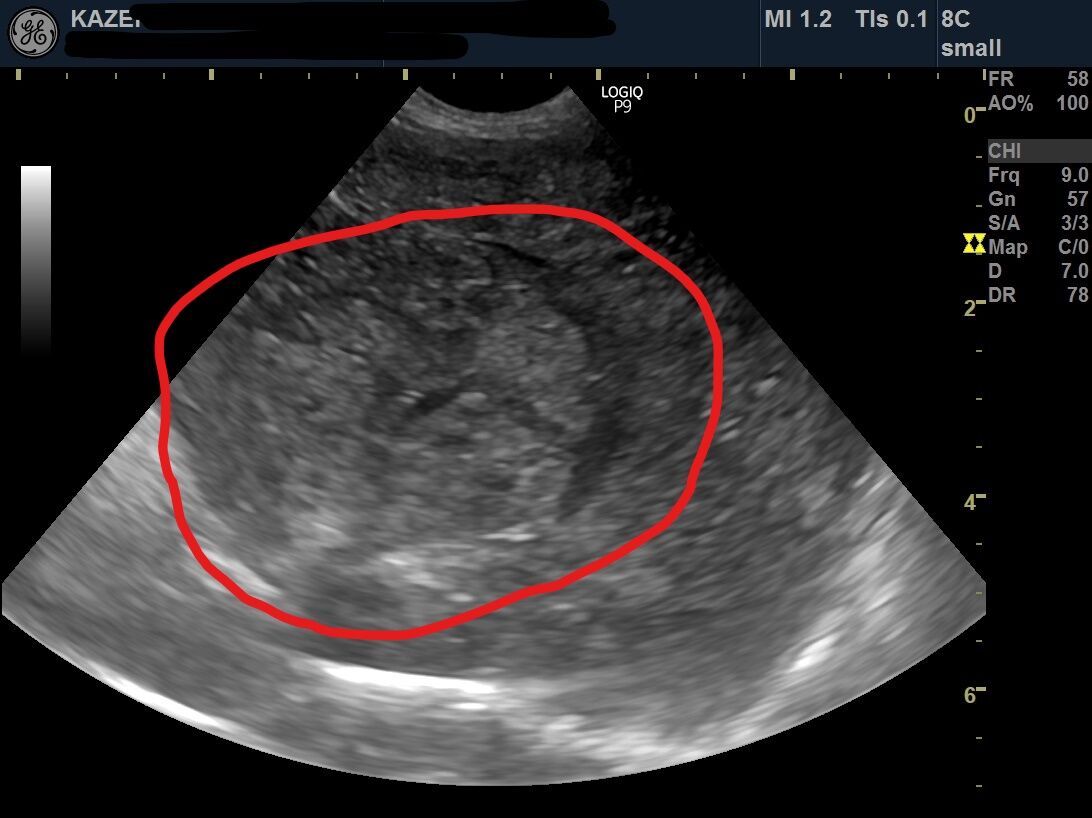

犬 肝臓 腫瘍 エコー

犬 肝臓 腫瘍 エコー-犬の肝臓腫瘍~末期の症状と余命~ 内臓 (肝/脾/腎/他)の腫瘍, 肝細胞癌 肝細胞癌, 肝臓腫瘍 Tweet お腹のなかで最も大きい臓器は肝臓です。 そして最も多くの仕事をしているのも肝臓です。 そ肝細胞癌は犬の原発性肝臓腫瘍の中でもっと も多く見られる腫瘍で,肝臓腫瘍の50%にもな る肝細胞癌の53~%はマス状型で16~25% は結節状型,最大19%がび漫性型である2 マス状型肝細胞

動物がん診療サポート 池田雄太 はじめに 犬の肝臓腫瘍には様々なタイプが発生するが、その多くは肝細胞癌であり約70%を占める。 肝細胞癌は進行が比較的緩やかであり、無症状のことも多いた原因や症状、予防法などについて解説|いぬのきもちWEB MAGAZINE 獣医師監修|犬の肝臓病とは? 原因や症状、予防法などについて解説 肝臓は「沈黙の臓器」ともいわれ、病状があらわれにく犬の肝臓腫瘍の手術例 肝臓にできた肝細胞癌の手術例をご紹介します。 肝臓は胆のうを境に左区域と右区域に分けられます。 一般的に右区域にある腫瘍を摘出する手術の方が左区域のものより難